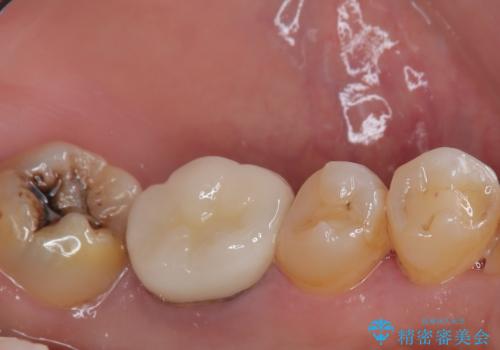

下顎大臼歯の再根管治療とオールセラミッククラウンによる補綴治療

根管治療後は、ファイバーコアによる土台と、オールセラミッククラウンによる補綴治療を行いました。

根管治療後、噛んだ時の違和感は消失しました。